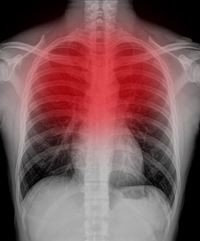

. A szívizomgyulladás myocarditis bármely életkorban előfordulhat de alapvetően ritka betegség 1-10 főt érinthet évente 100 000 ember közül. A szívizomgyulladás egy viszonylag ritka betegség de a koronavírus-fertőzés esetleges szövődményeként egyre többet hallani rólaDr. Jellemző tünetei a szúró mellkasi fájdalom légzési.

A szívizomgyulladás vagy myocarditis a szívizom gyulladásos megbetegedése12 Többféle kórokozó által is kiváltott betegség így vírusok legfőképp Coxsackie- vagy adenovírusok. Mint már említettük az iparosodott társadalmakban a szívizomgyulladásos esetek többségéért a vírusfertőzés a felelős. Az amerikai CDC megpróbálta.

A karidológiai MR-vizsgálat eredményeiből kiderült hogy 37 sportolónál a teljes állomány 23 százalékánál megvoltak a COVID-19 miatti szívizomgyulladás kritériumai. A szívizomgyulladás tünetei a betegség előrehaladott állapotától függően változnak. Szívizomgyulladás myocarditis A myocarditis a szívizomszövet gyulladása amelynek hátterében általában valamilyen fertőző ágens áll leggyakrabban vírus ritkábban baktérium.

A szívizomgyulladás okai. A szívizomgyulladás ahogy a neve is mutatja a szív simaizmát érintő gyulladás amelynek több kiváltó oka lehet és bármilyen életkorban előfordulhat. A szívizomgyulladás a szívizom gyulladásos megbetegedése amelyet többféle kórokozó által kiváltott betegségA szívizomgyulladás lényege hogy a gyulladásnak.